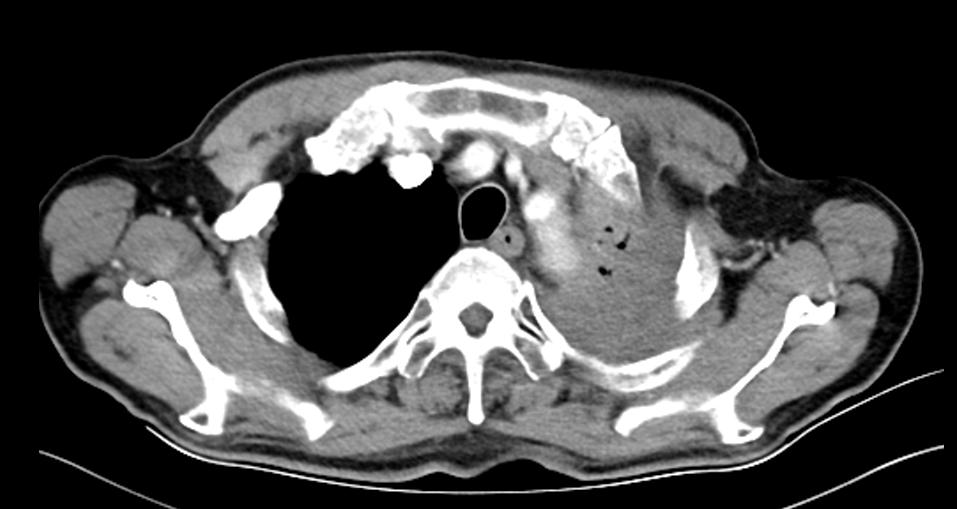

2019-10-16 胸腹部CT示:左肺上叶占位并周围阻塞性炎症、节段性肺不张,纵隔及双肺门多发小及增大淋巴结。肝内小囊性灶,建议增强扫描。考虑双侧壶腹型肾盂。前列腺増生、钙化。肠壁多发钙化:考虑血吸虫性肠道改变。

2021-09-29胸腹部CT示:检查结果左肺上叶占位并周围阻塞性炎症、节段性肺不张:较前进展,相应左肺上叶肺动脉受侵,纵隔及双肺门多发小及增大淋巴结,建议继续治疗及复查。支气管炎、肺气肿伴双肺多发肺大泡同前,右肺下叶少许炎症、右侧胸膜增厚同前,左测少许胸腔积液,建议复查。左侧第4肋骨质破坏,建议结合全身骨扫描。主动脉及部分冠脉钙化灶。左侧颈背部皮下囊性灶较前相仿,建议结合临床。肝内小囊性灶同前;前列腺増生、钙化。提示血吸虫性肠病,建议结合临床病史。